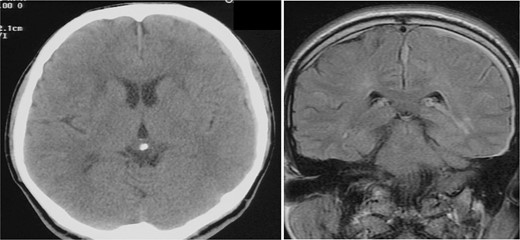

A man in his fifties presented with sudden severe headache that showed no improvement. Initial CT at another hospital revealed SDH, prompting referral to our institution. Head CT demonstrated left SDH including the interhemispheric fissure (Fig. 1). 3D-CTA performed at the referring hospital revealed ⁓5-mm saccular aneurysms at the left ICA and right basilar-superior cerebellar artery junctions, along with left A3-A4, and right A2-A3 aneurysms (Fig. 2). Preoperative FLAIR imaging showed no evidence of SAH (Fig. 3). As the initial 3D-CTA inadequately captured the distal portions of the ACA, we performed repeat imaging upon admission, which revealed an additional left A3A4 DACA aneurysm. However, due to the DACA aneurysm being smaller than the ICA aneurysm, definitive determination of the rupture source was not possible.

CT (left) axial image of the brain and MRI (right) fluid-attenuated inversion recovery coronal image from the referring hospital. SDH is visible on both images, without evidence of SAH. SDH is also visible in the interhemispheric fissure on MRI.